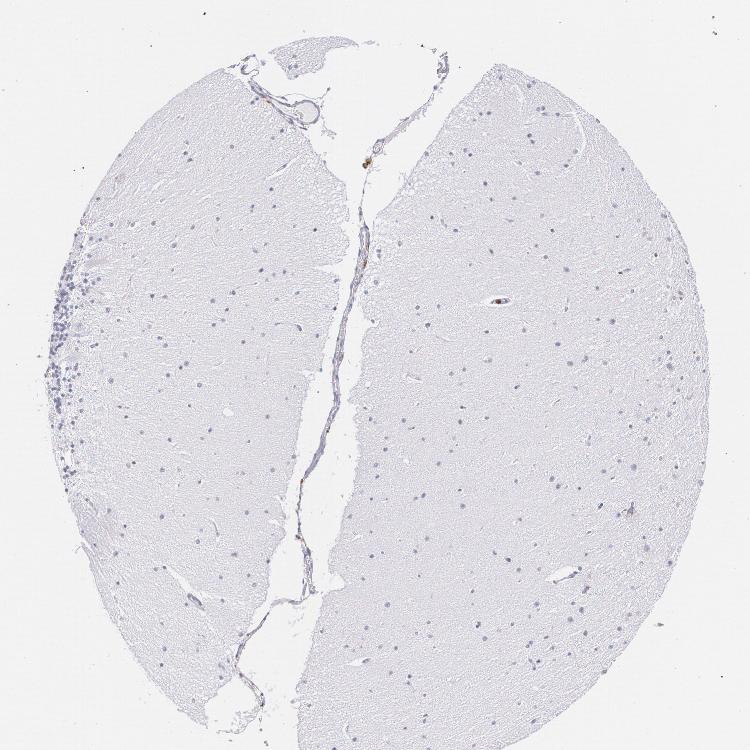

BRAIN CEREBELLUM Show tissue menu

CEREBELLUM - Expression summary

CEREBELLUM - Antibody stainingi

Antibody staining in the annotated cell types in the current human tissue is reported as not detected, low, medium, or high, based on conventional immunohistochemistry profiling in selected tissues. This score is based on the combination of the staining intensity and fraction of stained cells.

Each image is clickable and will lead to virtual microscopy that enables deeper exploration of all samples and also displays staining intensity scores, fraction scores and subcellular localization as well as patient and tissue information for each sample.

Antibody HPA000440Antibody CAB000052Antibody CAB002800Antibody CAB056154Antibody CAB068221Antibody CAB080251

Purkinje cells Not detectedNot detectedNot detectedNot detectedNot detectedNot detected

Cells in granular layer Not detectedNot detectedNot detectedNot detectedNot detectedNot detected

Cells in molecular layer Not detectedNot detectedNot detectedNot detectedNot detectedNot detected